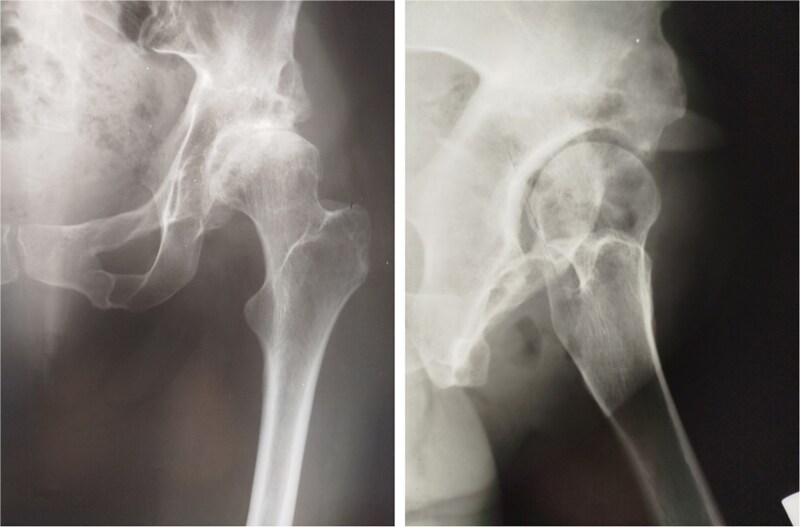

一位35岁的女性髋臼发育不良患者接受了Pol Le Cœur三重骨盆截骨术(TPO)。28年后,她出现疼痛的终末期髋关节骨关节炎,并接受了全髋关节置换术(THA)。植入加压式无骨水泥髋臼杯和骨水泥直股柄,无并发症。在13年的随访中,髋关节x线片显示没有假体不稳定和假体松动的迹象。TPO可能不能完全预防髋关节骨关节炎的进展。本例患者在截骨术后28年出现进行性终末期骨关节炎,需要THA。Pol Le Cœur对于患有低度骨关节炎的年轻成人,TPO是一种治疗症状性髋臼发育不良的可行选择,可有效延缓髋关节假体植入。TPO后混合THA在中期随访中能获得非常满意的临床和影像学结果。

A 35-year-old female patient with acetabular dysplasia underwent a Pol Le Cœur triple pelvic osteotomy (TPO). Twenty-eight years later, she presented with painful end-stage hip osteoarthritis and underwent total hip arthroplasty (THA). A press-fit cementless acetabular cup and a cemented straight femoral stem were implanted without complications. At 13-year follow-up, hip radiographs revealed no signs of prothesis instability and no signs of implant loosening. TPO may not completely prevent the progression of hip osteoarthritis. In this case, the patient developed progressive end-stage osteoarthritis 28 years after the osteotomy, requiring THA. Pol Le Cœur TPO is a viable treatment option for symptomatic acetabular dysplasia in younger adults with low-grade osteoarthritis, effectively delaying hip prosthesis implantation. Hybrid THA after TPO can yield very satisfactory clinical and radiographic outcomes at mid-term follow-up.